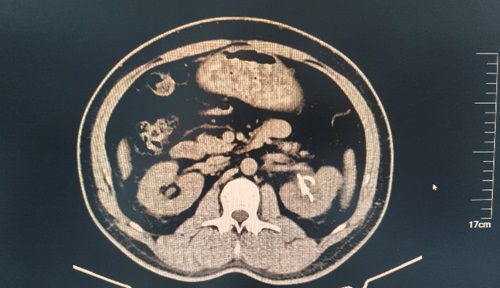

患者,男,46岁,主因左侧腰腹部间断性疼痛10天。于我院查泌尿系CT示左肾鹿角状结石、右肾结石收入院。后在可控负压吸引下行输尿管软镜钬激光碎石术治疗肾结石。

术前视图如下:

由CT可见:患者左侧肾盂输尿管支架术后改变,较术前左肾结石体积基本消失,原左侧输尿管上段结石、左肾盂-输尿管结合部扩张较前未见。